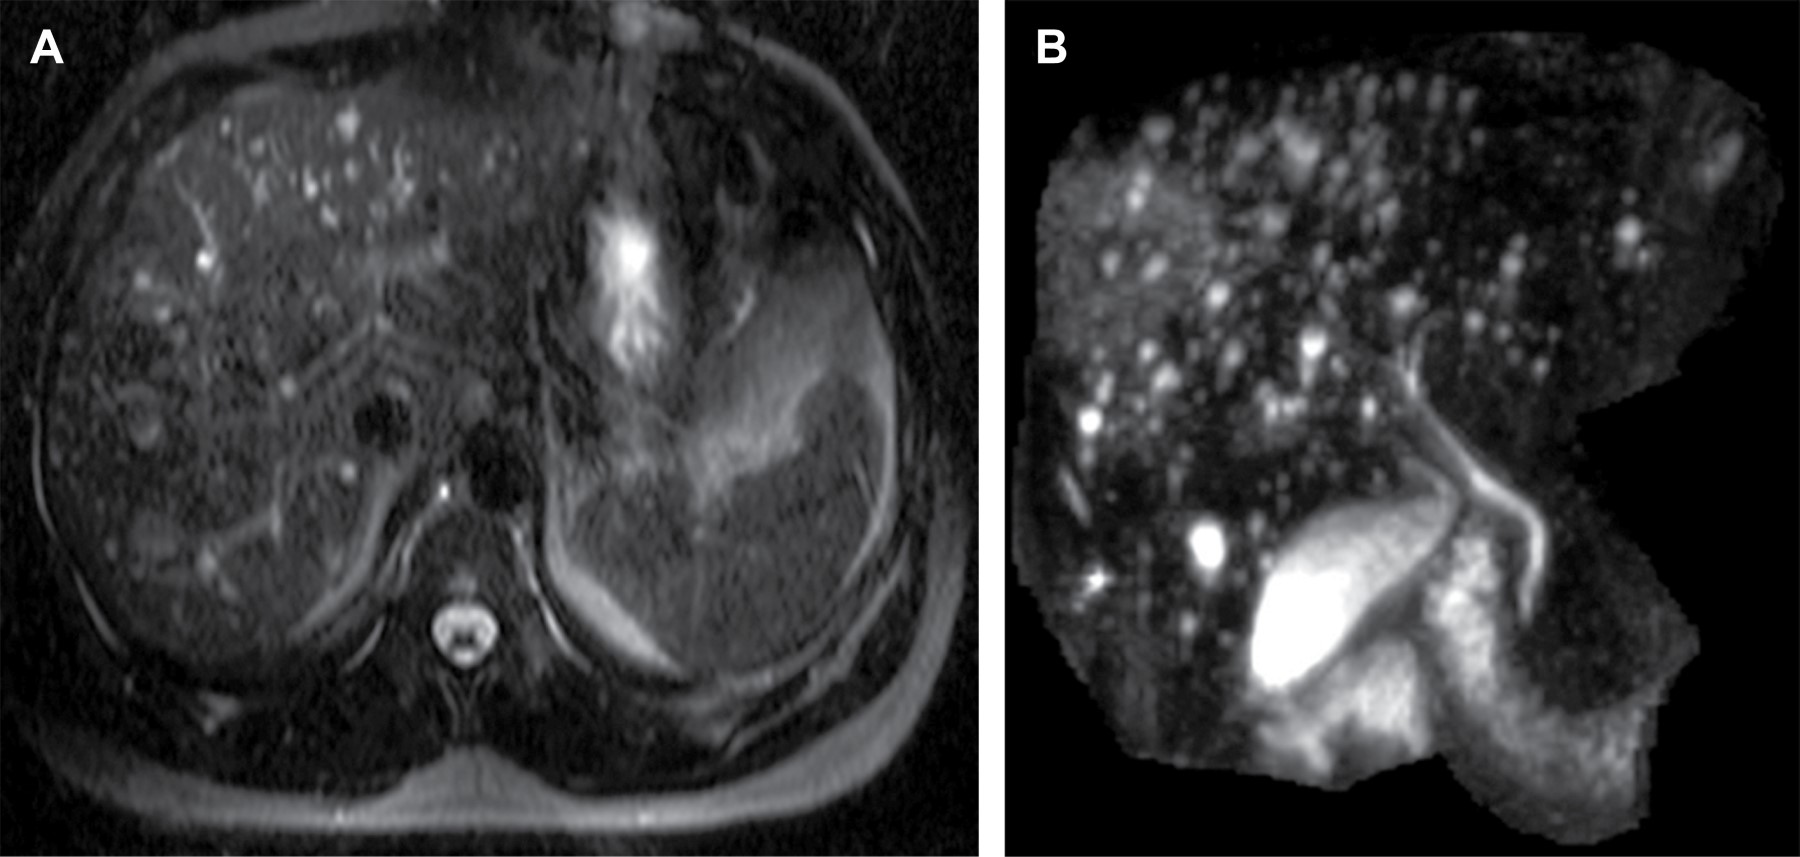

Se presentan imágenes de tomografía contrastada de abdomen, donde se identifica hígado aumentado de tamaño, con parénquima heterogéneo, con múltiples imágenes hipodensas de aspecto ovoideo y de distribución difusa y esplenomegalia (Figura 1). La enfermedad de Caroli fue descrita en 1958 por el médico francés Jacques Caroli, también conocida como "ectasia cavernosa comunicante congénita del árbol biliar". Es una enfermedad congénita rara, de patrón autosómico recesivo, que afecta a uno de cada millón de habitantes con mayor prevalencia en la población femenina, con una frecuencia con respecto a los varones de 1.8:1.1-4

El diagnóstico por imagen se puede realizar por diversos estudios tales como ultrasonido y tomografía computarizada (TC); sin embargo, la colangiopancreatografía por resonancia magnética (MRPC, por sus siglas en inglés) es actualmente el método de elección debido a su elevada especificidad y sensibilidad.2,4 En estudios realizados con TC podemos observar la mencionada dilatación de los conductos biliares intrahepáticos como imágenes hipodensas, de bordes definidos y de densidad líquida, distribuidas de manera difusa o focal (Figura 1).1,2 Las imágenes obtenidas por medio de MRPC mostrarán múltiples lesiones de naturaleza quística de diversos tamaños que se comunican con el árbol biliar y que presentan una alta intensidad, al ser imágenes potenciadas en T2 (Figura 2).1,3

Figura 1